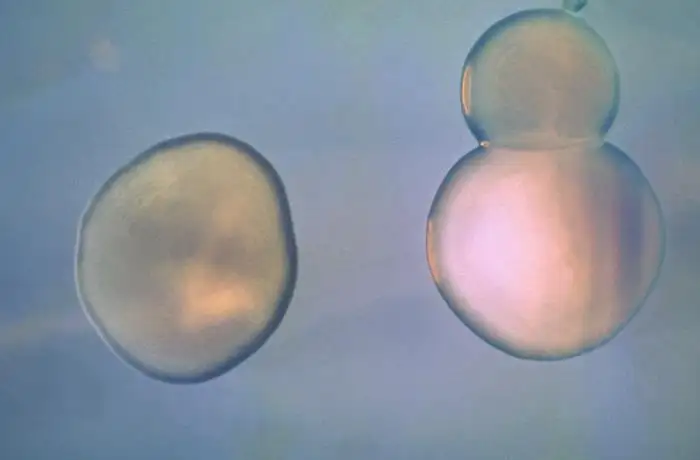

霍乱疫苗的研发同样经历了漫长而曲折的道路。第一种霍乱疫苗于1885年在西班牙研发成功,是一种灭活的注射型疫苗。然而,这种疫苗的保护效果有限,副作用明显,需要多次注射,在资源有限的环境中难以推广。二十世纪八十年代,口服霍乱疫苗开始出现,其中最成功的是一种由灭活霍乱弧菌细胞组成的疫苗,被称为Dukoral。这种疫苗于1991年在瑞典首次获得许可,此后在多个国家获得批准。然而,霍乱疫苗的广泛使用面临着诸多挑战——冷链运输的要求、两剂接种的方案、保护期的限制——使得疫苗在霍乱流行地区的覆盖率长期处于较低水平。